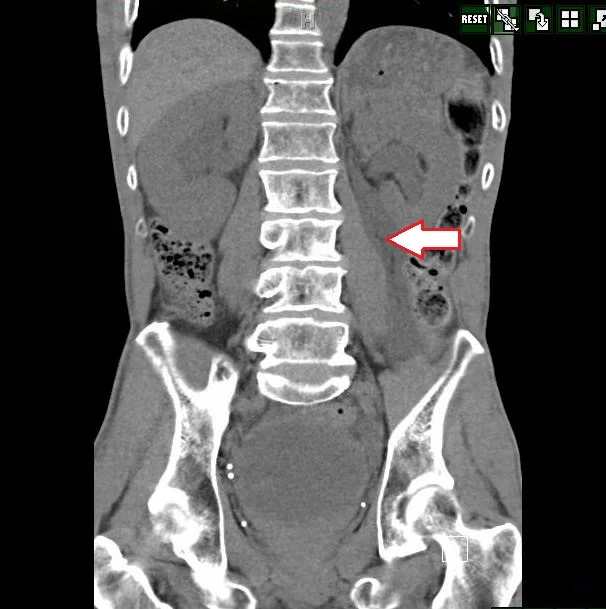

A 64 y.o. diabetic presents with L flank pain and elevated blood sugar. His CT is below.

What is the reason for his pain?

Our patient had a rupture of his L kidney caused by obstruction. Forniceal rupture occurs from several causes.  In a study of 100 cases of kidney rupture:  obstructing stones caused 74% of ruptures, with malignant external compression of the ureter causing 8.3%,  Benign extrinsic compression caused 1.9%, pelvic ureteral obstruction caused 1.9% with vesicoureteral obstruction causing the same number.  They listed 3.7%  as iatrogenic (i.e. during stent placement)  and bladder obstruction in 0.9%.  Bladder obstruction was the cause in our patient.  Several patients had unusual causes of obstruction, for example, an aortic aneurysm. In children obstruction is often at the pelvis of the kidney.

The most common cause of kidney rupture, obstructing stones were also studied and the average stone size was 4 mm.  Once the kidney ruptures, either the urine becomes encapsulated forming a urinoma or becomes free fluid in the peritoneal cavity, urinary ascites.

The treatment is relieving the obstruction; in the case of our patient a foley was placed.  In cases where a stone is present, a stent is often placed. Doppler US can indirectly provide a measure of renal pelvis pressure.  Thanks to Drs. Schwarz, Ruoff and Kane for the case.